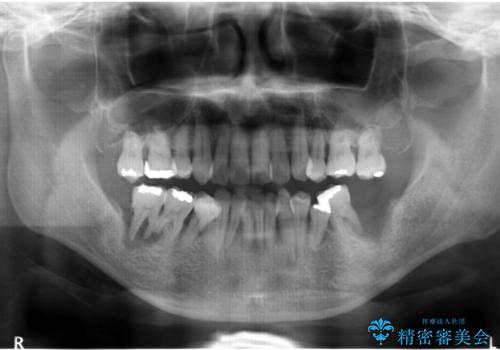

インプラント治療を併用した全顎歯周病治療

- 「仕事のリタイヤに目処がつき、今後は自分の健康にお金をかけたい。しっかりと食事ができる口腔内環境にしてほしい。」と全体的な治療を希望され来院されました。

全体的に重度の歯周病が認められ、抜歯が必要な部位はインプラント治療を、残すことのできる歯には再生治療を含めた歯周病治療を行い全体的な治療を進めてきます。